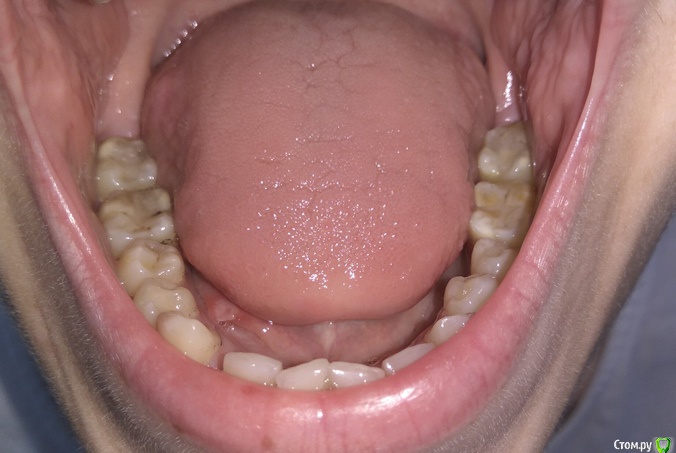

Добрый день. Уважаемые специалисты, прошу совета, БС была установлена в 2015 году, тогда же удалены молочные клыки, ортодонт сказал, что можно вытянуть, но как оказалось не все это могут сделать. Был сделан доступ к постоянным клыкам с небной стороны, приклеены кнопки, установлены лигатуры в области первых премоляров. В 2015-2016 была беременность. Примерно в феврале 2017 лигатуры были заменены на микроимплантаты в области первого моляра с небной стороны и установлены металлические лигатуры. В итоге - движение не наблюдается. Вопрос - можно ли еще пробовать их вытянуть или же делать радикально - удаление и имплантация, или после удаления можно сместить премоляры и моляры вперед?